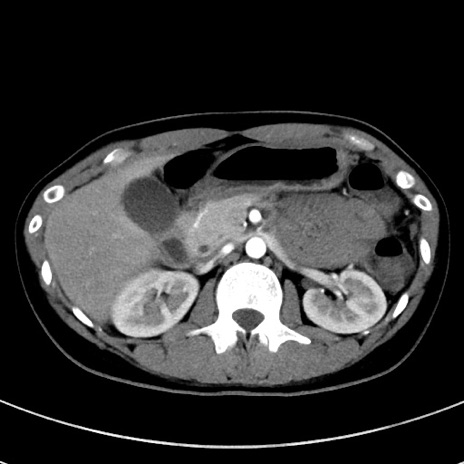

症例17(横断像)

【症例】20歳代女性

【主訴】嘔吐、下腹部痛

【現病歴】昨日夕食後に嘔吐し下腹部痛が出現。本日になっても嘔吐持続し改善しないため来院。

【身体所見】意識清明、BT 37.2℃、BP 108/67mmHg、腹部:平坦、やや硬、下腹部正中から右にかけて圧痛あり、反跳痛軽度あり、tapping pain(+)。

【データ】WBC 13600、CRP 14.94